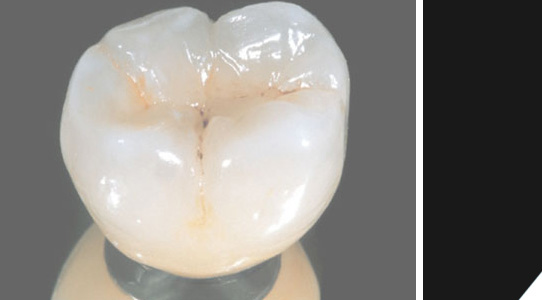

Eine perfekte Krone - würden Sie den Unterschied sehen?